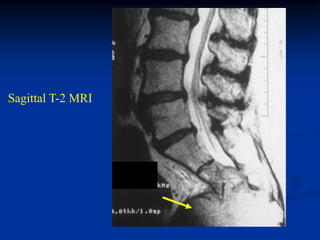

Sagittal T-2 MRI

Photomic